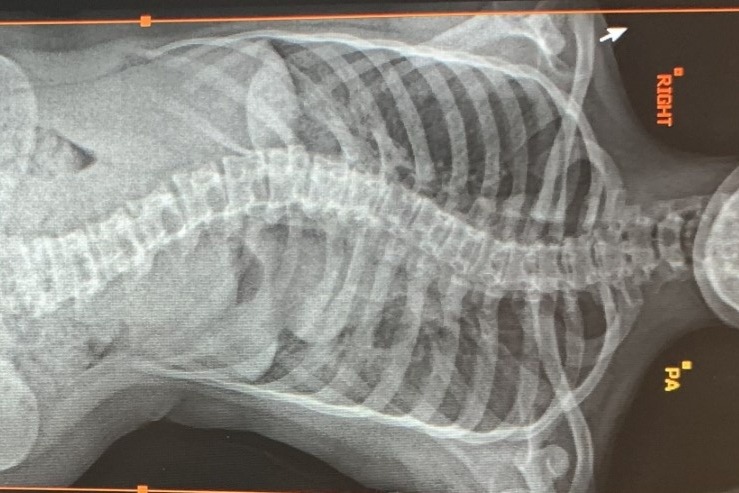

Holi has complained more and more of pain recently, and now finds it hard to walk for too long without needing to rest. We thought that her back looked more lop-sided too so we took her for an x-ray. We were heart-broken to see that her curve has progressed to 56 degrees in just a year. No wonder she is in pain.